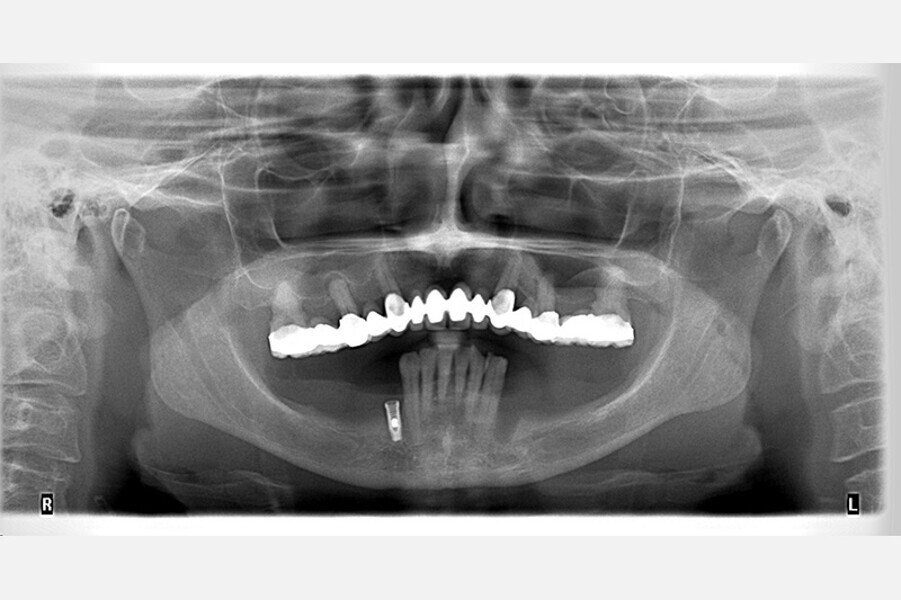

Fig. 16. Rx Pre-operatoria, Prótesis híbrida inmediata con 6 años de evolución y Rx Control a los 6 años.

Fig. 17. Rx Pre-operatoria, Prótesis híbrida inmediata con 6 años de evolución y Rx Control a los 6 años.

Fig. 18. Rx Pre-operatoria, Prótesis híbrida inmediata con 6 años de evolución y Rx Control a los 6 años.